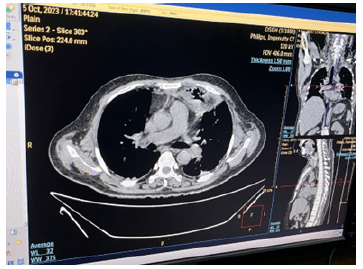

Chest radiograph showed slight widening of mediastinum. Blood for hemoglobin was 11.2gm%; total WBC count was 9.9 X109 /L (Neutrophils 88.1%, Lymphocyte 9.5%, Monocyte 2.4%); platelet count was 36 X109/L; ESR was 40mm per 1sthour; serum creatinine was 4.9mg/dl (0-1.3mg/dl); blood urea was 244.3mg/ dl (10-50mg/dl); serum sodium was 132 ; potassium was 4.4; chloride was 98; total bilirubin was 15.6 mg/dl (0.2-1.0mg/dl); Aspartate aminotransferase was 65U/L (9-48U/L); LDH was 502U/L (200-480U/L). Blood sugar (105.6mg%) and Hb A1 C were normal. Blood for retroviral serology was negative; serology for hepatitis B and C were negative. Computed tomography (CT) neck showed right cervical lymphadenopathy with some areas of break down suggestive of abscess. CT chest revealed features of mediastinitis and mediastinal abscess; they were in continuation with pre-tracheal fascia as seen in CT neck findings (Figures 2-12).

Figure 5: CT chest showing multiple abscess with surrounding opacities in the anterior mediastinum suggestive of mediastinitis and mediastinal abscess, and minimal left pleural effusion.

Figure 6: CT chest showing larger abscess in the anterior mediastinum with minimal left pleural effusion.

Figure 7: CT chest showing larger abscess with surrounding inflammation in the anterior mediastinum with minimal left pleural effusion.

Figure 9: CT chest showing mediastinitis and rounded opacity with air speck at the level of trachea bifurcation.